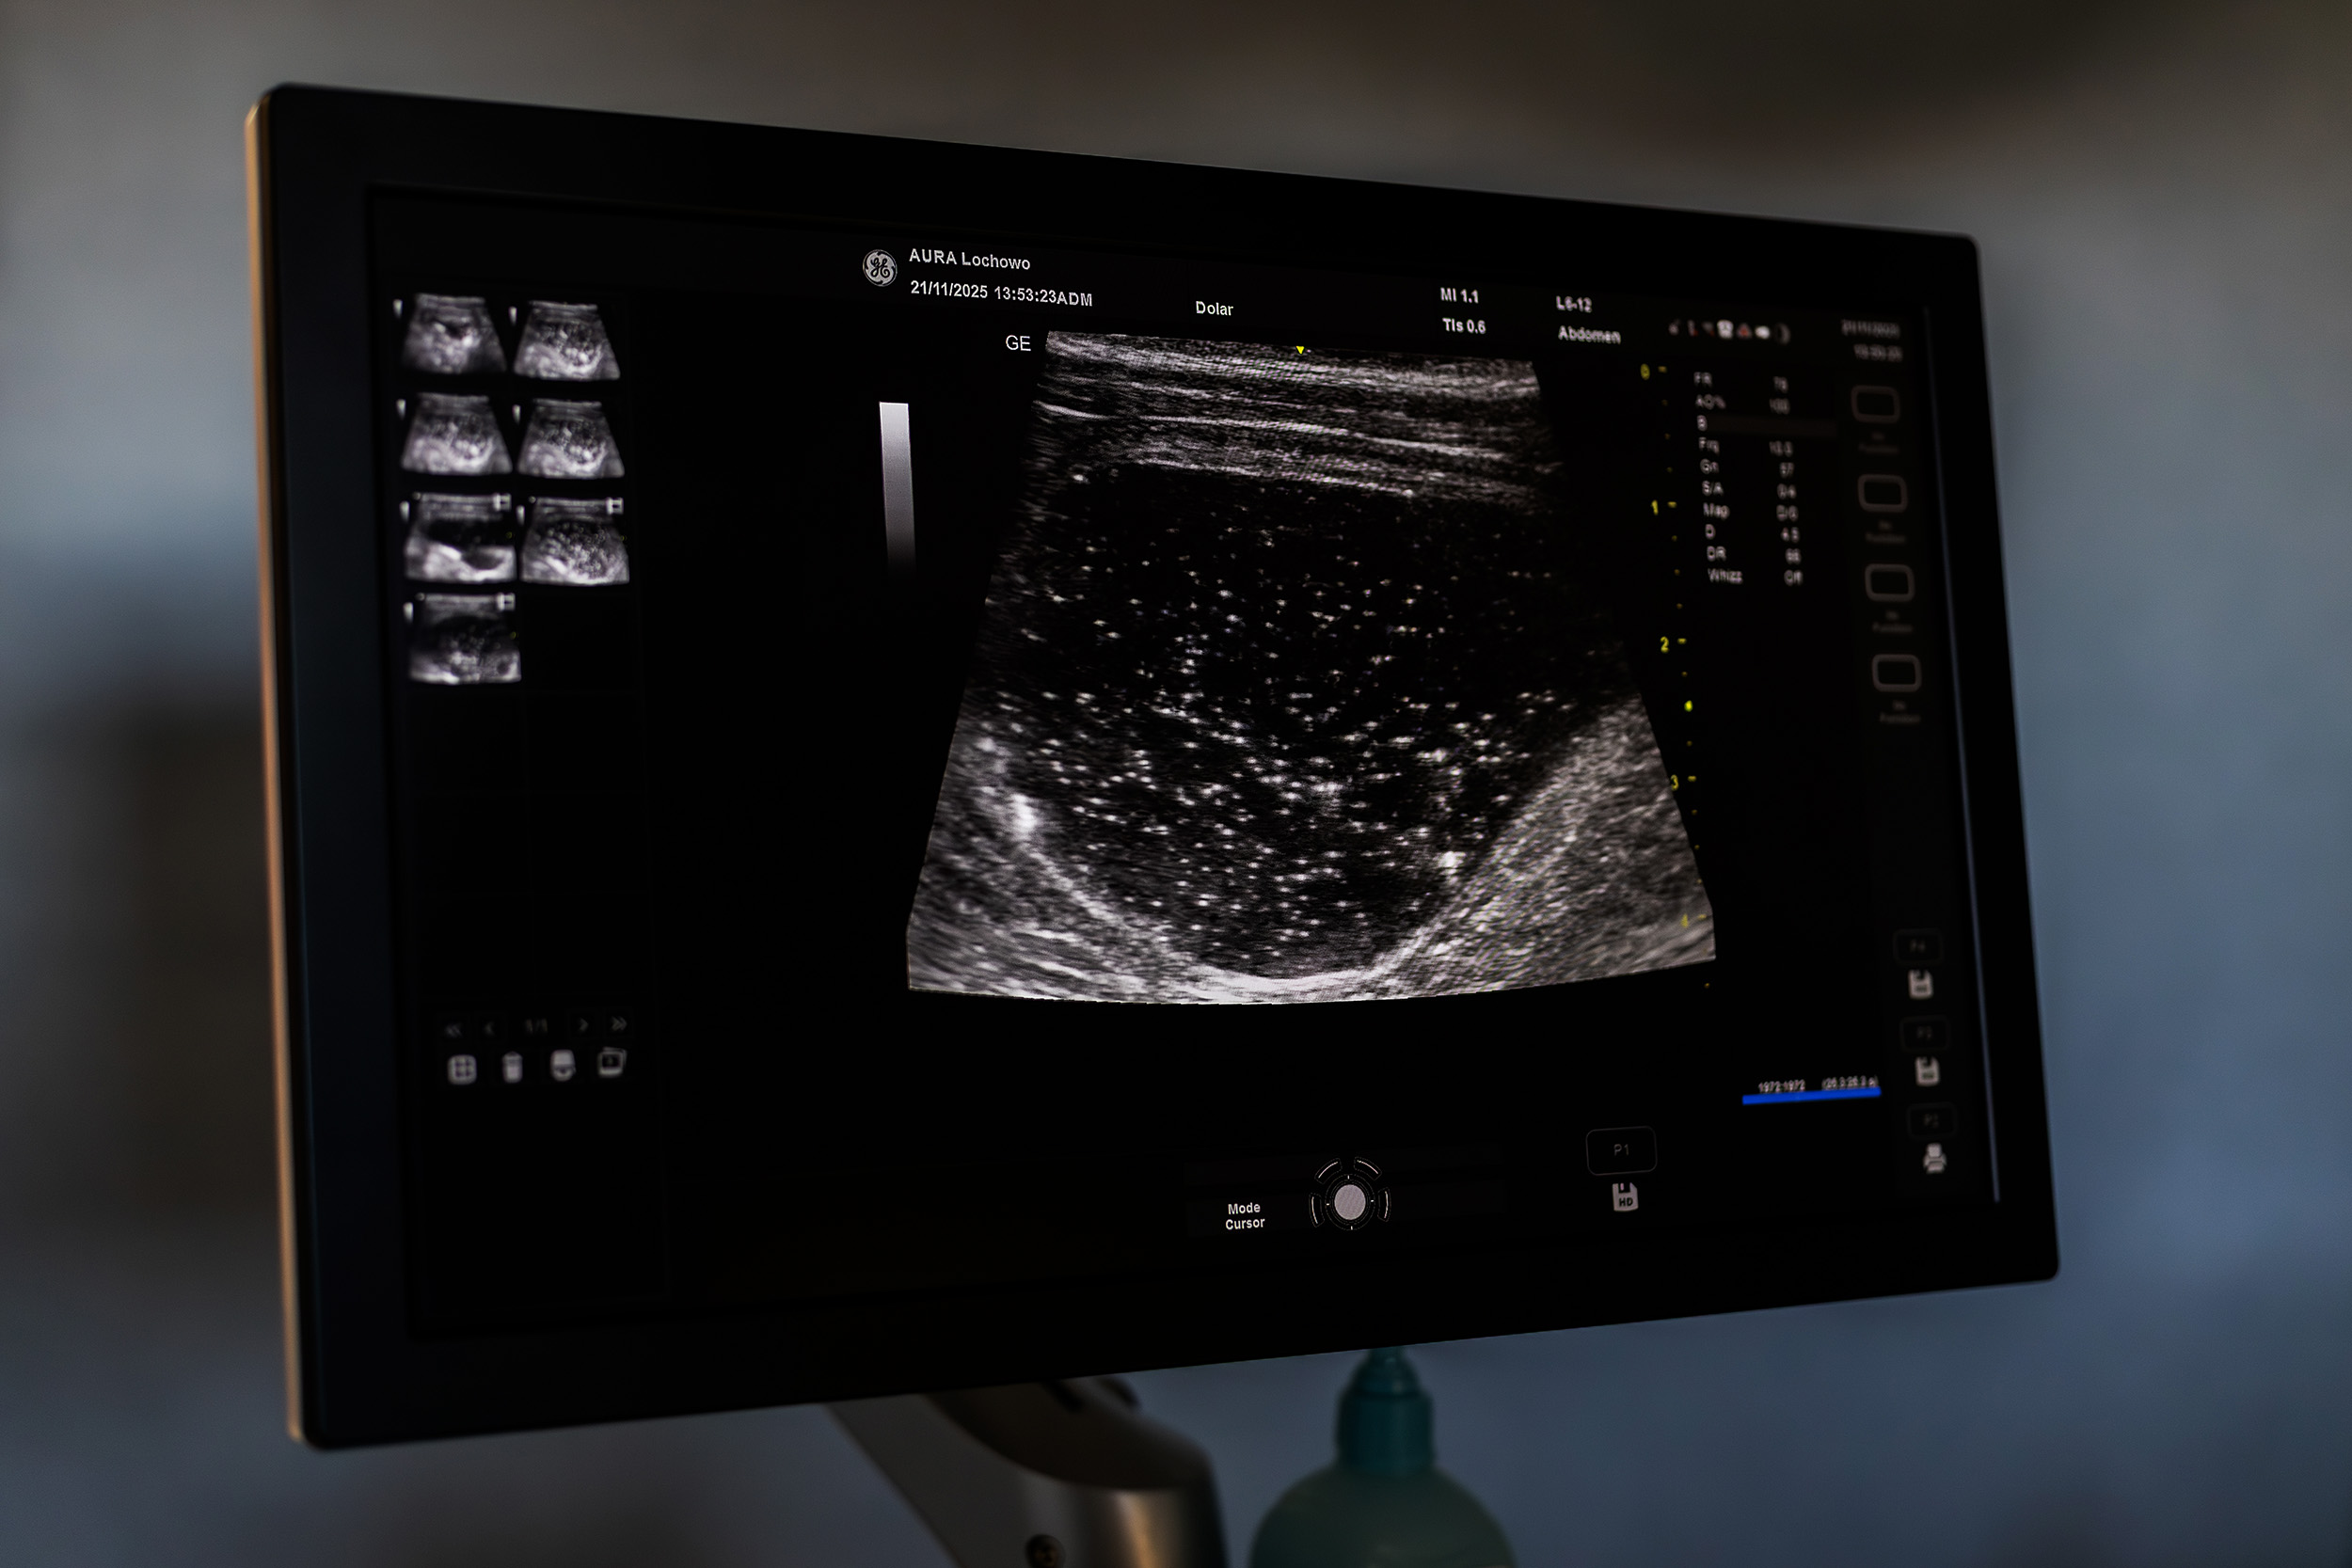

Badanie  ultrasonograficzne (USG) to szybka, powszechna i nieinwazyjna metoda obrazowania tkanek miękkich, naczyń krwionośnych i narządów. W trakcie badania specjalna sonda wysyła  wiązkę fal ultradźwiękowych, które odbijają się od różnych tkanek i powracają do aparatu, a otrzymane dane są przekształcane w widoczny na monitorze obraz w czasie rzeczywistym. Samo badanie jest całkowicie bezpieczne i w większości przypadków nie wymaga znieczulenia, dzięki czemu znajduje ono zastosowanie w wielu dziedzinach medycyny weterynaryjnej.